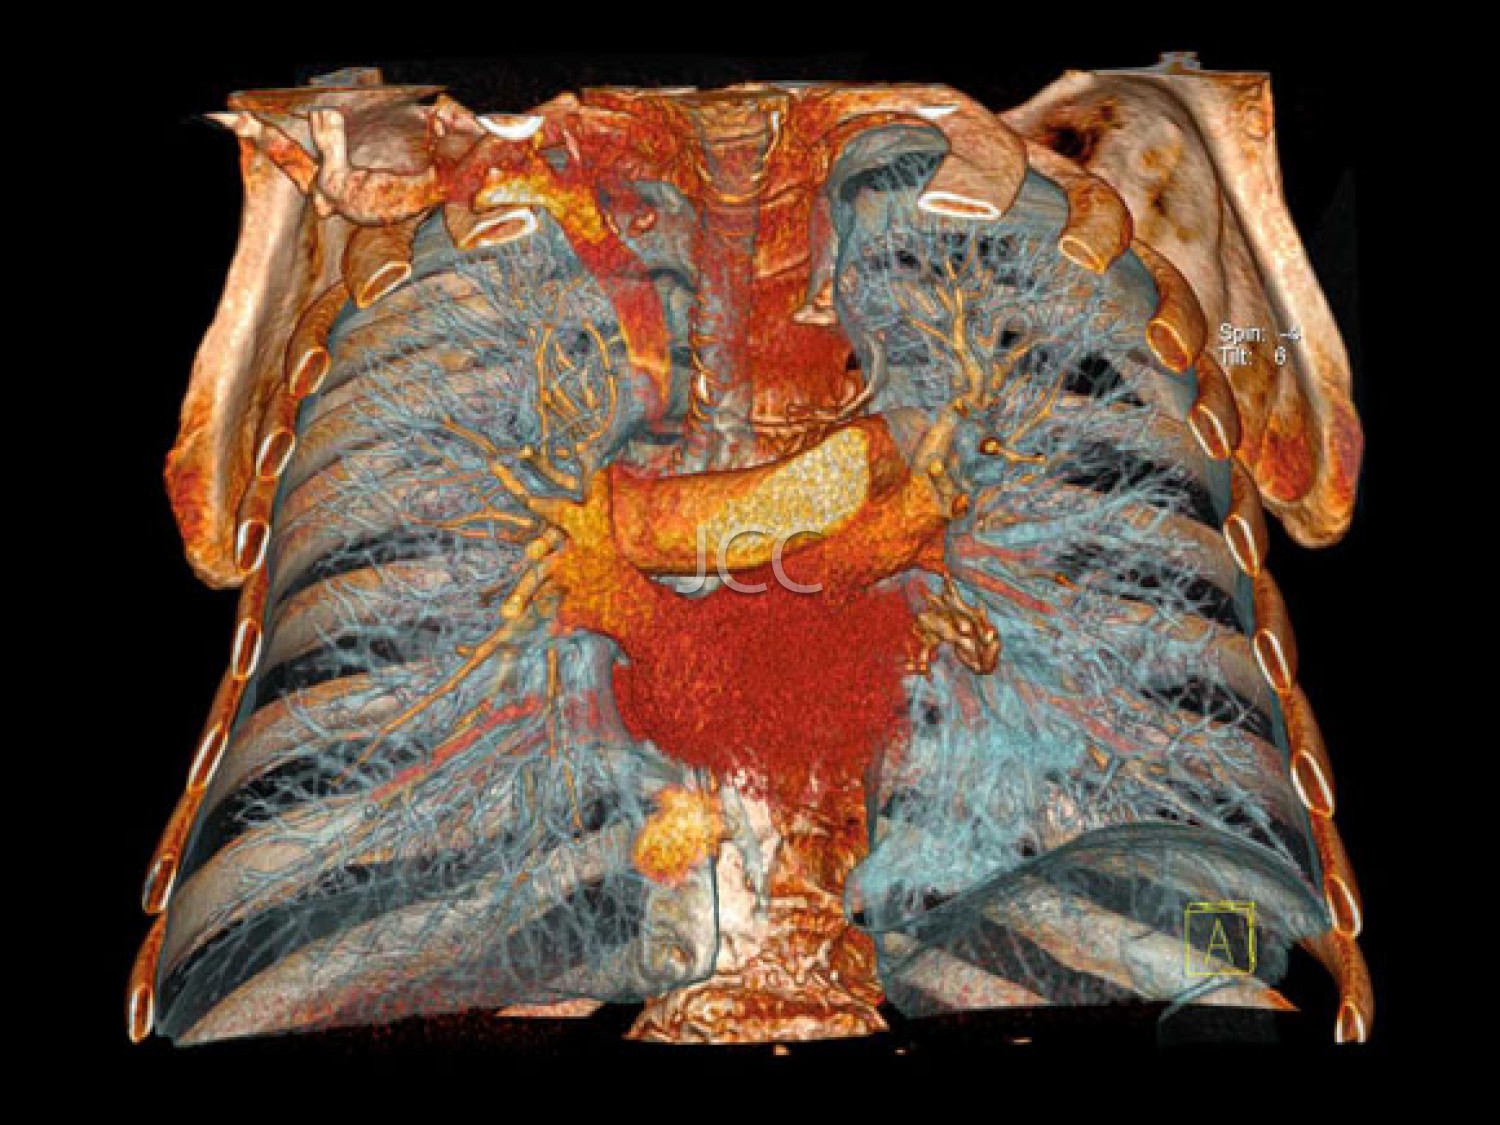

IMAGEM PREVENTIVA

Pela 1ª vez na história da medicina, através da tecnologia multi-detector, com dupla ampola e ressonância magnética de última geração 3 tesla, é possível, de modo não invasivo e capacidade diagnóstica comprovada, efectuar o screening de processos patológicos, para prevenção de doença cardíaca, neoplasias e acidente vascular cerebral – AVC. Salienta-se que com o nosso equipamento de TAC dual source - 256 cortes -  a dose de radiação é  muito baixa (cerca de 10 vezes inferior à dose dos equipamenos de TAC de 64 cortes).  Os dados obtidos nestes equipamentos de ultima geração são tratados em estações de trabalho de alto nível, que utilizando sistemas CAD e de visualização tridimensional, resulta em informação detalhada e muito rigorosa.

O conjunto destes exames com este tipo de equipamento constitui a modalidade de escolha para o estudo imagiológico do corpo humano, através de angiografia não invasiva do coração, do cérebro e dos vasos do pescoço, colonoscopia virtual por TAC assim como a avaliação dos restantes orgãos e estruturas ósseas do tórax, do abdomen e da pélvis, o estudo da próstata no caso do homem e da mama no caso da mulher.

• Angio TC das Coronárias